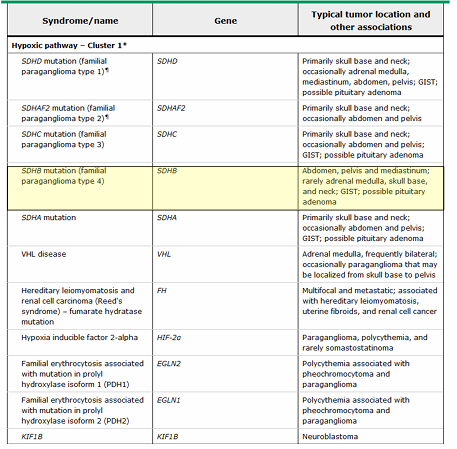

tubules with thiazide and loop diuretics

hypotensive disorders with hypokalemic metabolic alkalosis- Gitelman syndrome, Bartter syndrome